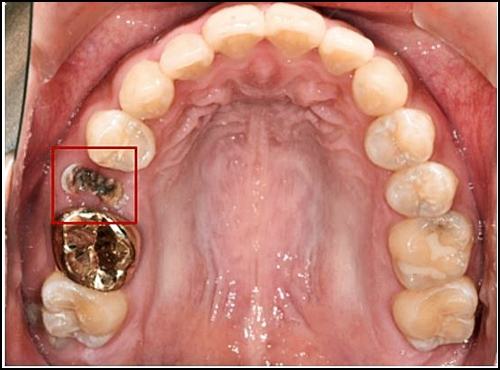

특히 크라운 치료 후 내부 충치 진행 및 신경에 염증이 생겨 치아를 뽑아야 하는 상황이 발생할 수도 있으므로 주의하셔야만 합니다.(아래 사진을 참고해 주세요)

앞쪽 치아 크라우 제거한 모습

충치로 인해 치관마저 상실되어 자연치아를 살리기 어려워

결국 임플란트 치료 진행하였습니다.